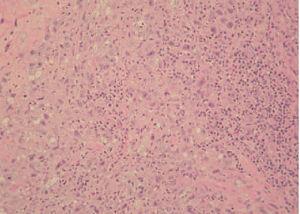

Una mujer de 73 años, diagnosticada de enfermedad de Hodgkin en estadio IV-E, de tipo depleción linfocitaria, presentaba una lesión osteolítica en el ala sacra izquierda que englobaba partes blandas y raíces nerviosas y otra masa en la quinta vértebra lumbar. La paciente consultó por la presencia, en la misma región lumbosacra izquierda, de unas placas eritematosas, de 1-2 cm de diámetro, muy infiltradas a la palpación y de tiempo de evolución indeterminado (fig. 1). Se practicó una biopsia cutánea, en la que se pudo observar un infiltrado tumoral que afectaba a la dermis profunda y al tejido celular subcutáneo, respetando la dermis superficial y la epidermis. La neoplasia estaba constituida por abundantes células mononucleadas atípicas (células de Hodgkin) y por células multinucleadas correspondientes a células de Reed-Sternberg (fig. 2), acompañadas por un escaso infiltrado de células inflamatorias no neoplásicas compuesto por linfocitos, eosinófilos e histiocitos predominantemente, en una estroma desmoplásica (fig. 3). Las células neoplásicas fueron positivas para CD30, CD15 y aisladas células se tiñeron con antígeno de membrana epitelial (EMA). No se obtuvo inmunotinción positiva para el antígeno leucocitario común (CD45), para marcadores B (CD20 y CD79a), marcadores T (CD3, CD43, CD4 y CD8), ni para el resto de anticuerpos monoclonales empleados (creatincinasa, HMB-45, CD68, CD21 y ALK).

Fig. 3.Infiltrado inflamatorio acompañante con linfocitos, histiocitos y eosinófilos. (Hematoxilina-eosina, ×20.)